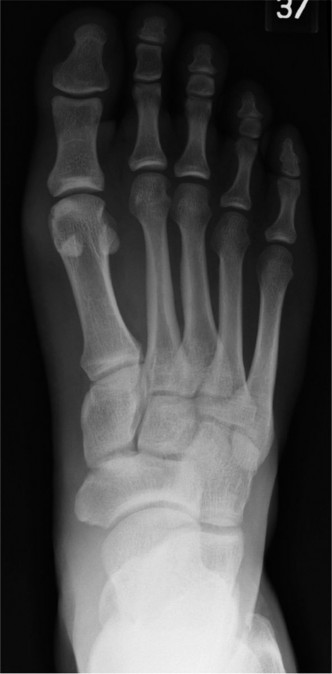

A 21-year-old, collegiate football player noted acute medial forefoot pain when he axially loaded a dorsiflex…